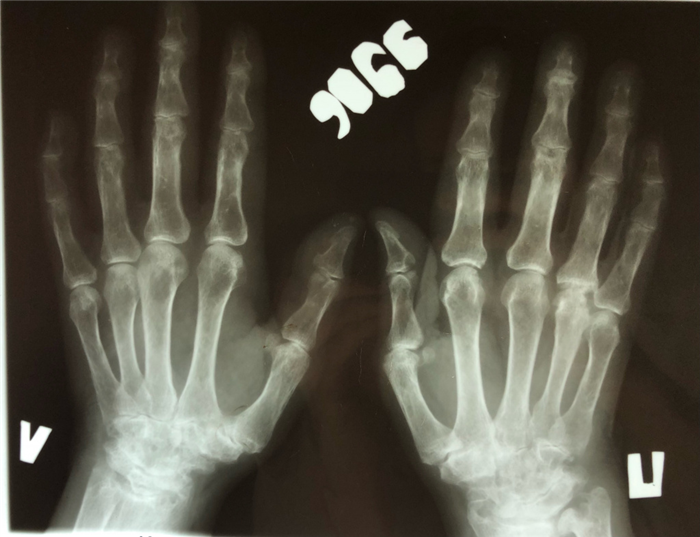

(Слева) Рентгенография кистей в ЗП проекции: определяются сужение суставных щелей пястно-фаланговых суставов и ульнарная девиация пальцев. Также в обеих кистях определяется сужение суставные щелей всех запятых суставов и эрозивные изменения шиловидных отростков локтевых костей. Картина типична для ревматоидного артрита.

Рис. 3.1. Рентгенография суставов кистей. На обзорной рентгенограмме обеих кистей определяется выраженное сужение суставной щели лучезапястных суставов, пястно-фаланговых, проксимальных межфаланговых суставов с образованием эрозий, выражнный околосуставной остеопороз, лизис шиловидных отростков локтевых костей, анкилоз костей запястья с двух сторон. (Изображения из личного архива, разрешено к публикации).

Рис. 3.2. У пациентки с длительным анамнезом ревматоидного артрита определяются выраженные артриты лучезапястных суставов, пястно-фаланговых суставов обеих кистей. (Изображения из личного архива, разрешено к публикации).

Рентгенография суставов — достоверный, но на ранних стадиях заболевания имеющий низкую диагностическую ценность, метод исследования. Околосуставной остеопороз как признак первой рентгенологической стадии РА развивается как минимум в течение нескольких недель. А костные эрозии и узуры — наиболее важный симптом РА — являются поздним признаком и могут обнаруживаться лишь спустя много месяцев. Тем не менее рентгенография суставов обязательна при любом подозрении на РА.

В первую очередь выполняется снимок кистей вне зависимости от степени субъективных и объективных признаков их поражения. Эрозии и сужение суставной щели проксимальных межфаланговых суставов обеих кистей рук наиболее типичны для РА. Они могут прогрессировать субклинически и, следовательно, их обнаружение дополняет картину даже при нерезко выраженных признаках воспаления. Рентгенологические изменения в крупных суставах считаются менее специфичными для РА. Тем не менее, особенно при серонегативных формах болезни, исследование костей таза может быть диагностически значимым.